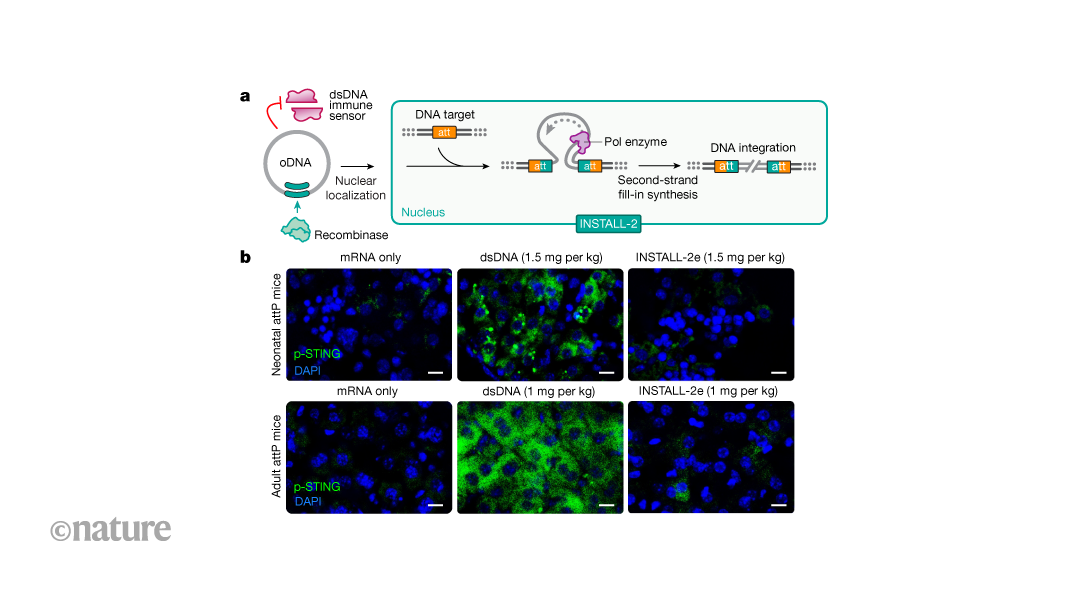

Genome editing that avoids immune detection to integrate large DNA sequences

Nature, Published online: 18 March 2026; doi:10.1038/d41586-026-00730-6A genome-editing approach called INSTALL combines single-stranded DNA molecules that e...

In vivo site-specific engineering to reprogram T cells - Nature

Nature, Published online: 18 March 2026; doi:10.1038/s41586-026-10235-xStable and cell-specific transgene expression can be achieved through in vivo site-spe...